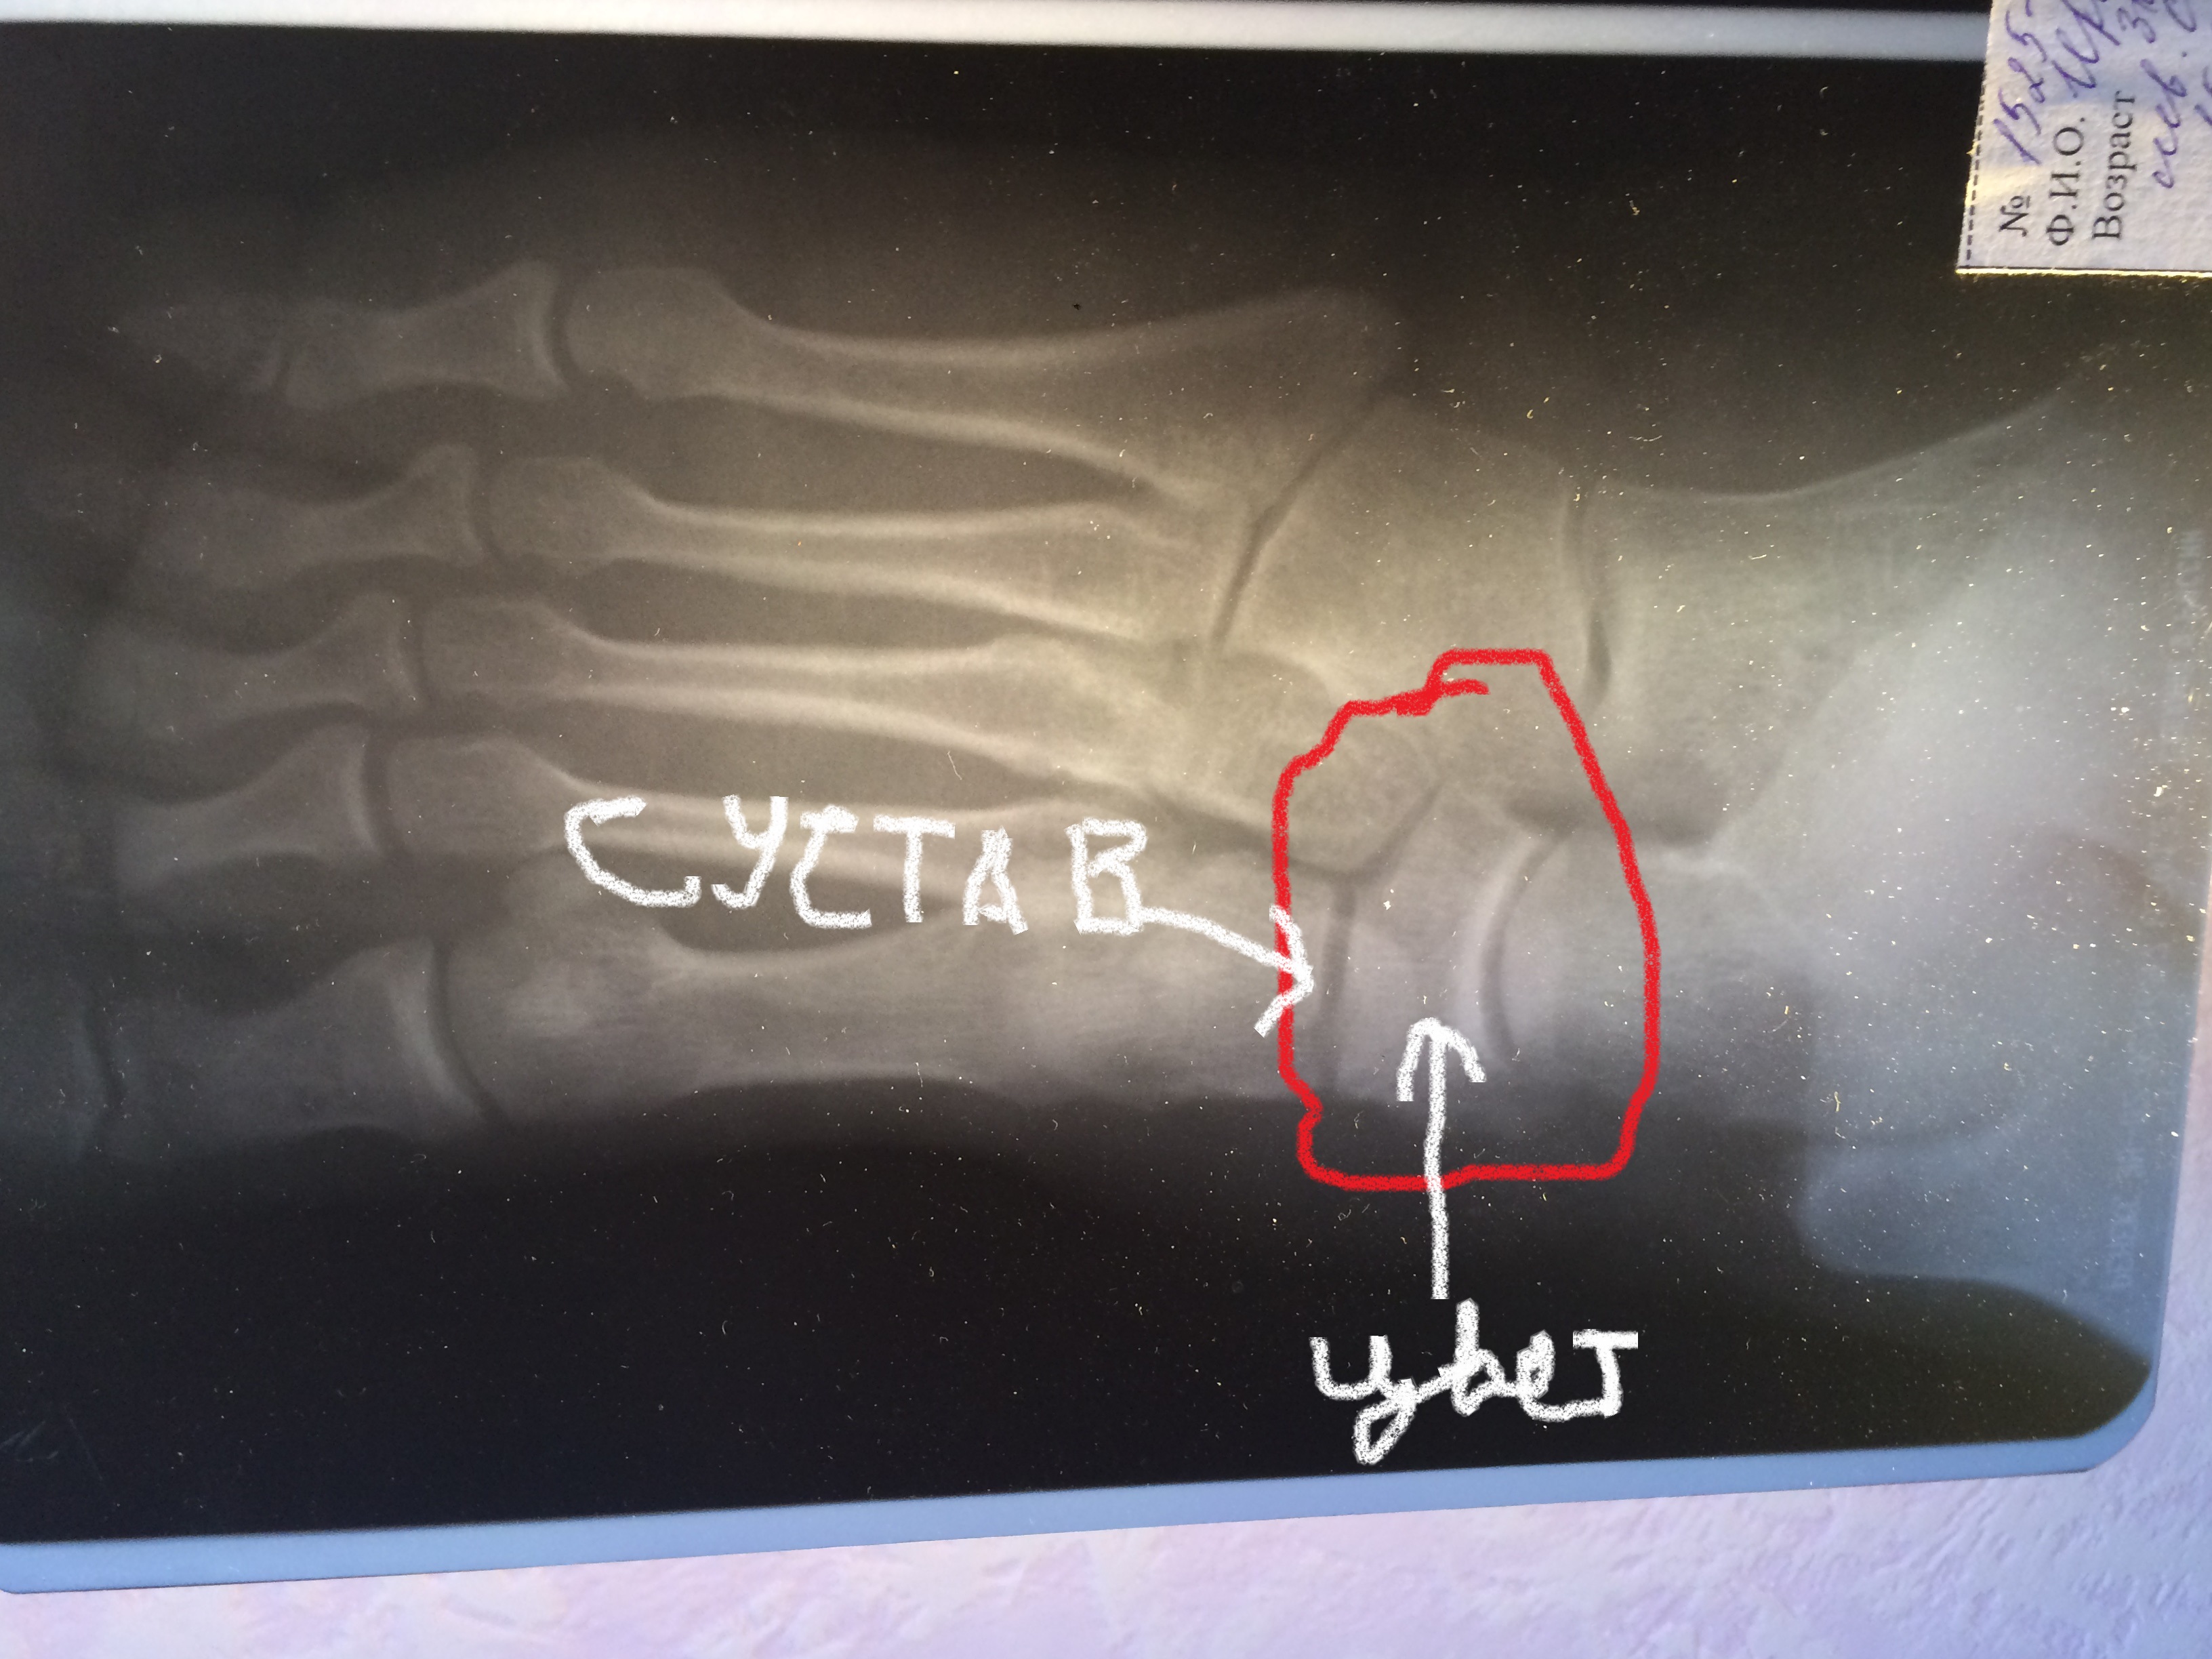

Блог Как "СanadaPeptides" ногу залечила=]

Тема в разделе "Персональные блоги", создана пользователем Kabran, 30 июн 2017.